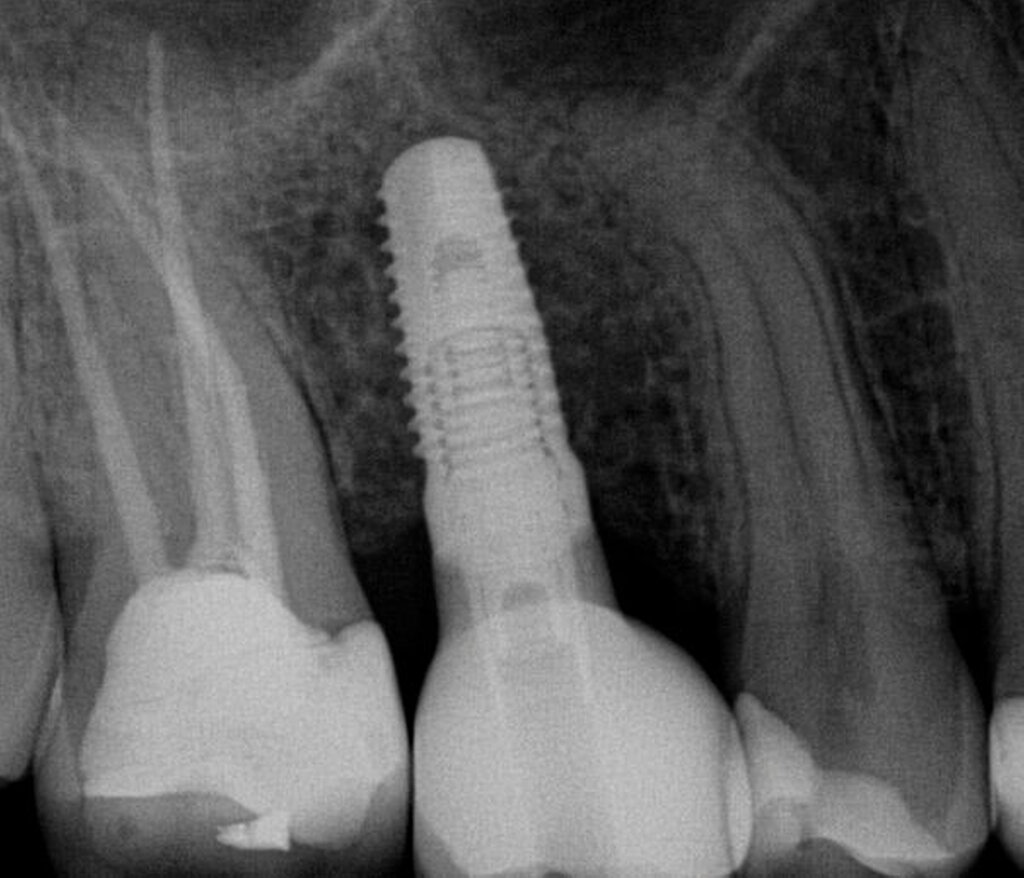

In der IPS wurde das Implantat in Regio 16 unterhalb des geplanten Zahnersatzes eingefügt. Aufgrund des verfügbaren Knochenangebots wurde für den vorgestellten Patientenfall aus der Datenbank der IPS das Implantat CAMLOG SCREW-LINE Promote plus (CAMLOG Vertriebs GmbH, Wimsheim) mit einem Durchmesser von 4,3 mm und einer Länge von 11 mm ausgewählt (Abbildung 2). Die angestrebte transokklusale Verschraubung bedingte die Ausrichtung des Schraubenkanals mittig in der Okklusalfläche des Wax-ups. Bei Frontzähnen empfiehlt sich für eine transokklusale Verschraubung deren Ausrichtung palatinal der Inzisalkante.

Im vorliegenden Patientenfall wurde die Implantation statisch navigiert mithilfe einer Bohrschablone und einer voll geführten Insertion durchgeführt (Abbildung 3). Dafür wurde der STL-Datensatz der Bohrschablone nach der Konstruktion in der IPS durch einen spezialisierten Mitarbeiter des Servicepartners DEDICAM (CAMLOG Vertriebs GmbH, Wimsheim) für die Bohrschablone zur Verfügung gestellt. Die Herstellung der Schablone erfolgte mithilfe eines 3-D-Druckers (Form 3, Formlabs GmbH, Berlin) im zahntechnischen Labor der Charité – Universitätsmedizin Berlin. Alternativ hierzu kann die Schablone auch vollständig fertig gestellt beim entsprechenden Anbieter bestellt werden.